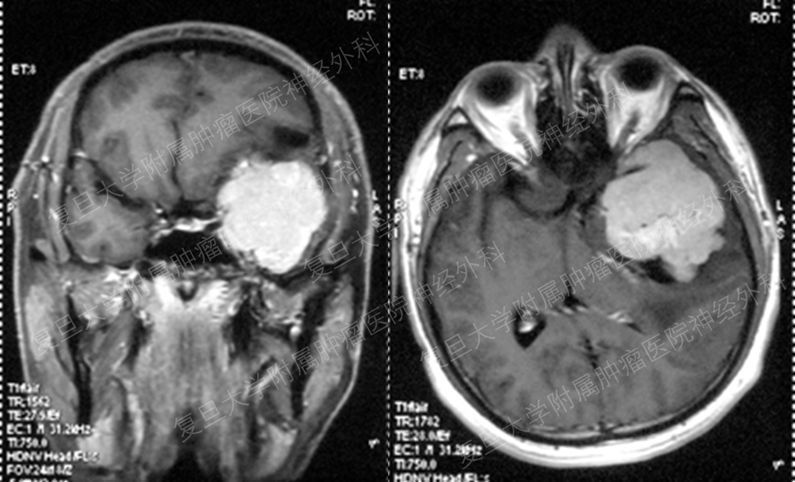

血管母細(xì)胞瘤在顱內(nèi)的總體發(fā)病率不算太高,但是在后顱窩這個(gè)特定的部位卻并不少見。雖然血管母細(xì)胞瘤最常見的生長(zhǎng)部位是小腦,但是偶爾也可以生長(zhǎng)于脊髓、腦干和大腦。因?yàn)檠苣讣?xì)胞瘤在小腦生長(zhǎng)并壓迫小腦組織,所以出現(xiàn)頭痛、嘔吐、惡心,走路不穩(wěn),平衡障礙等顱內(nèi)壓增高和小腦功能異常的癥狀。在顱內(nèi)腫瘤中,一般名稱中帶有“母”字的腫瘤都不是什么好的東西,基本都是惡性的腫瘤,如膠質(zhì)母細(xì)胞瘤,星形母細(xì)胞瘤,髓母細(xì)胞瘤等,都是惡性的腫瘤,這類腫瘤生長(zhǎng)速度快,即使手術(shù)切除加上放化療,也很容易復(fù)發(fā)甚至轉(zhuǎn)移,難以真正治愈。但是血管母細(xì)胞瘤卻是一個(gè)例外,血管母細(xì)胞瘤是良性的腫瘤,是可以通過手術(shù)切除而達(dá)到完全治愈的一個(gè)疾病。血管母細(xì)胞瘤常常是一個(gè)囊實(shí)性的病變,手術(shù)中通過徹底切除病變的實(shí)質(zhì)性結(jié)節(jié),就可以僅僅通過手術(shù)切除達(dá)到治療效果,而不需要后續(xù)的放化療。中山大學(xué)附屬腫瘤醫(yī)院柯超醫(yī)生團(tuán)隊(duì)近期完成的1例血管母細(xì)胞瘤就是這樣的一個(gè)病例,病人是一個(gè)52歲的女性患者,這種手術(shù)相對(duì)比較簡(jiǎn)單,病變切除只需要十幾分鐘,手術(shù)后病人不到1周就出院。但是他們?nèi)ツ晖瓿傻?例完全實(shí)質(zhì)性的小腦血管母細(xì)胞瘤就沒有這么簡(jiǎn)單了,病人是一個(gè)31歲男性,因?yàn)轭^痛而發(fā)現(xiàn)右側(cè)小腦完全實(shí)質(zhì)性血管母細(xì)胞瘤,手術(shù)前磁共振血管成像發(fā)現(xiàn)病變血供非常豐富,所以手術(shù)是分為兩步完成。首先進(jìn)行血管栓塞的手術(shù),部分阻斷病變的血供,減少開顱手術(shù)中大量出血休克的風(fēng)險(xiǎn);3天后再開顱手術(shù),徹底切除病變。經(jīng)過有計(jì)劃的分期手術(shù),雖然開顱手術(shù)中病變出血仍然很多,但是比起不經(jīng)過栓塞手術(shù)已經(jīng)是大大減少了,病人手術(shù)后很快就恢復(fù)了。這種完全實(shí)質(zhì)性的體積比較大的血管母細(xì)胞瘤如果位于腦干,則手術(shù)的難度和風(fēng)險(xiǎn)就更大了。當(dāng)然,也并不是所有的血管母細(xì)胞瘤都能通過腦部手術(shù)達(dá)到治愈的目的,大約20%腦或脊髓血管母細(xì)胞瘤是von Hippel-Lindau病的一個(gè)部分,這個(gè)疾病還可能同時(shí)伴有胰腺腫瘤,腎細(xì)胞癌,嗜絡(luò)細(xì)胞瘤等其他的腫瘤,這就需要多學(xué)科合作共同來處理了。